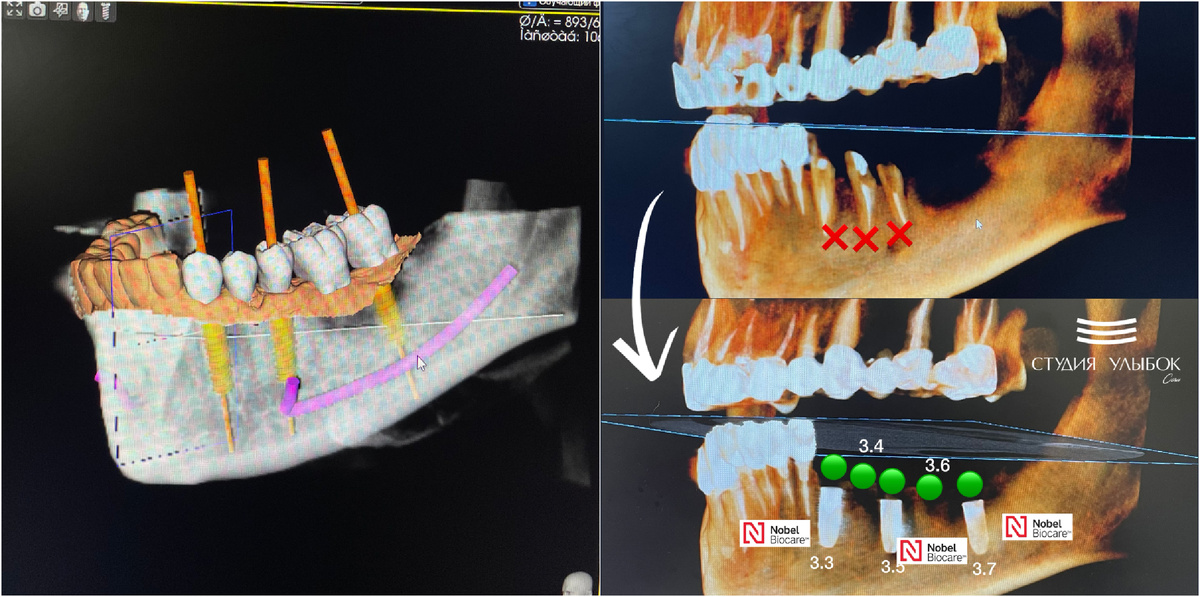

Кейс детальной имплантации. Пациент обратился с жалобой на перелом мостовидной конструкции снизу слева. Это протезирование 4-х летней давности, которое было произведено в другой клинике. После проведения диагностики и КЛКТ исследования мы увидели, что произошел перелом зубов: 33, 34, 35. Детальная имплантация Nobel (Швеция) была спланирована в цифровом протоколе и проводилась с помощью хирургического навигационного шаблона. Имплантаты были установлены по месту: 33, 35, 37. Зубы, которые расположены между установленными имплантами, 34 и 36, будут мостом будущей конструкции, которая будет иметь 3 опоры (это имплантаты) и 5 зубов (коронок). Операция по установке 3-х имплантатов Nobel Beocare была проведена очень точно и весьма успешно. Мы получили хорошую первичную стабильность. Дальнейший этап по протезированию, т.е. установки коронок на имплантаты спланирован по прохождению 3-х месяцев. Работа врача стоматолога-хирурга-имплантолога, Григория Эдуардовича Марванова. #имплантантынобель #с

Кейс детальной имплантации. Пациент обратился с жалобой на перелом мостовидной конструкции снизу слева. Это протезирование 4-х летней давности, которое было произведено в другой клинике.

После проведения диагностики и КЛКТ исследования мы увидели, что произошел перелом зубов: 33, 34, 35.

Детальная имплантация Nobel (Швеция) была спланирована в цифровом протоколе и проводилась с помощью хирургического навигационного шаблона. Имплантаты были установлены по месту: 33, 35, 37. Зубы, которые расположены между установленными имплантами, 34 и 36, будут мостом будущей конструкции, которая будет иметь 3 опоры (это имплантаты) и 5 зубов (коронок).

Операция по установке 3-х имплантатов Nobel Beocare была проведена очень точно и весьма успешно. Мы получили хорошую первичную стабильность. Дальнейший этап по протезированию, т.е. установки коронок на имплантаты спланирован по прохождению 3-х месяцев.